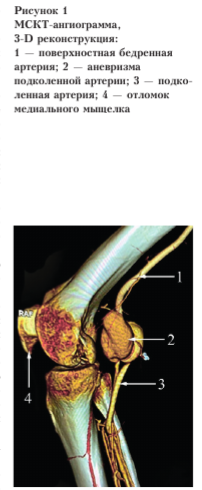

Ультразвуковое дуплексное сканирование (УЗДС) артерий нижних конечностей: ложная аневризма подколенной артерии справа; признаки реканализации берцового сегмента. Мультиспиральная компьютерная томография (МСКТ): частично тромбированная аневризма в правой подколенной области с формированием артериовенозной фистулы; внутрисуставной перелом заднего края медиального мыщелка правой бедренной кости со смещением отломка; металлическое инородное тело в мягких тканях правой подколенной области (рис. 1).

Прямая ангиография: справа подвздошно-бедренно-подколенноберцовый сегмент проходим; в области ПА — двухкамерная аневризма 37 х 32 мм и 21 х 35 мм.